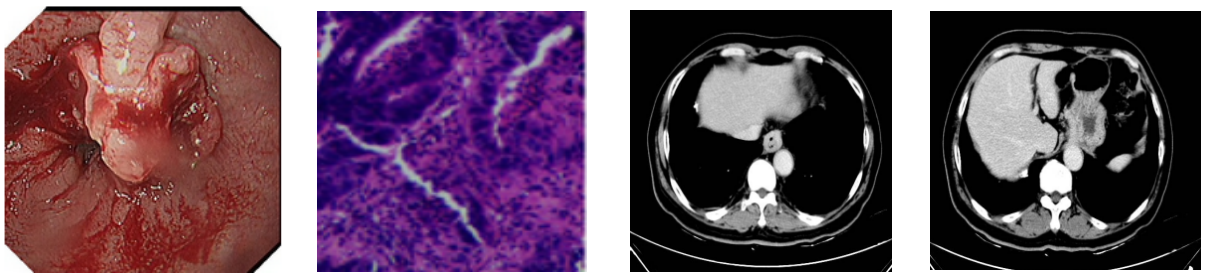

2021年11月患者无明显诱因出现进食哽咽,以粗硬食物为明显,无恶心、呕吐,无腹痛、腹胀,无后背部疼痛。于2021年12月29日就诊我院,门诊行胃镜检查,提示:食管下段可见菜花状肿物,环管腔约一周,触之易出血,镜身不能通过,取病理4块。病理回报:中分化腺癌。进一步完善胸部增强CT:食管下段及贲门管壁不均匀增厚,提示恶性肿瘤;食管下段周围、胃小弯侧多发淋巴结显示,部分肿大;纵隔内、右肺门多发淋巴结显示伴钙化。

1.png

诊断:食管下段中分化腺癌 腹腔淋巴结转移cT2N2M0 III期